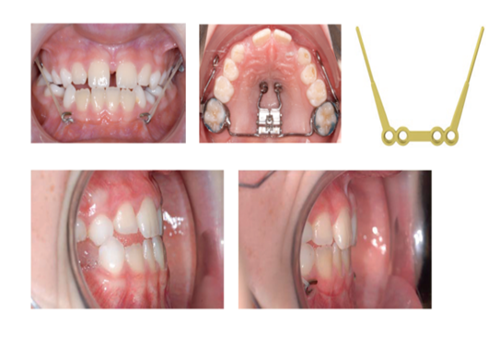

Skeletal forankring

Dit barn er henvist til Tand, Mund,- og Kæbekirurgisk afdeling for indsættelse af knogleforankring (mentoplate og ganeskruer) grundet en kæbeafvigelse (underbid). Operationen er første del af dit barns behandlingsforløb, som efterfølgende vil omfatte 12-18 måneder med elastiktræk mellem bøjlen i overkæben og krogene i underkæben (se fotos). Elastikkerne vil stimulere væksten af overkæben, så underbiddet gradvist bliver mindre for til sidst at forsvinde helt (se fotos).

Operationen foregår i fuld bedøvelse og efterfølgende kontroller og behandling foretages i kommunalt regi. I forbindelse med operationen indsættes 2 ganeskruer samt en lille metalskinne med kroge på underkæben, (se fotos). Det bliver syet i undermunden med tråde som er selvopløsende.

Sammenbid set fra siden før og efter behandling med elastiktræk.